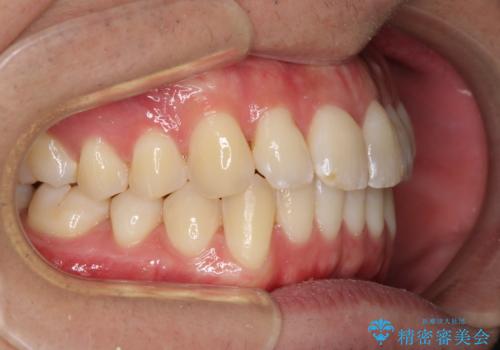

- 前歯のデコボコと若干口元が突出していることを気にして来院された患者様です。

全体的に軽微な叢生が認められ、口元もやや前方に突出していたため、インビザラインでのIPR(歯と歯の間を削る)と歯列全体の後方移動によって歯並びを整えることとしました。

上下ともに歯列の幅が狭かったため、側方に拡大することで前歯のデコボコや突出感を解消するためのスペースを獲得することができました。

歯並びが改善したことはもちろん、咬み合わせの改善まで実感することができ、患者様には大変満足していただけました。